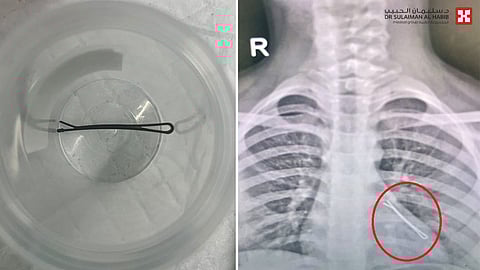

الذي قال أن الطفلة أسعفت إلى طواريء المستشفى، محولة من مركز طبي آخر وهي تعاني من إعياء شديد وعدم القدرة على التنفس، وفور وصولها خضعت لحزمة من الفحوصات الدقيقة، وأظهرت أشعة الصدر وجود مشبك معدني في الرئة اليسرى، فتقرر على الفور إجراء المنظار الرئوي لاستخراج الجسم الغريب بشكل عاجل، تجنباً لحدوث مضاعفات خطيرة.

وأضاف د. باسم أن الطفلة خضعت لعملية عاجلة باستخدام المنظار تحت التخدير العام واستغرقت 60 دقيقة ، حيث تم إدخال المنظار الرئوي الأحدث من نوعه على مستوى العالم عبر الفم دون الحاجة لأي قطع أو جراحة، وأظهر وجود الجسم عبارة عن مشبك للشعر في الفص السفلي للرئة اليسرى، وتم استخراجه بنجاح، ومضت العملية بسلاسة ووفقاً للخطة ودون أية مضاعفات، وخرجت الطفلة في نفس اليوم وهي بصحة جيدة ولله الحمد.